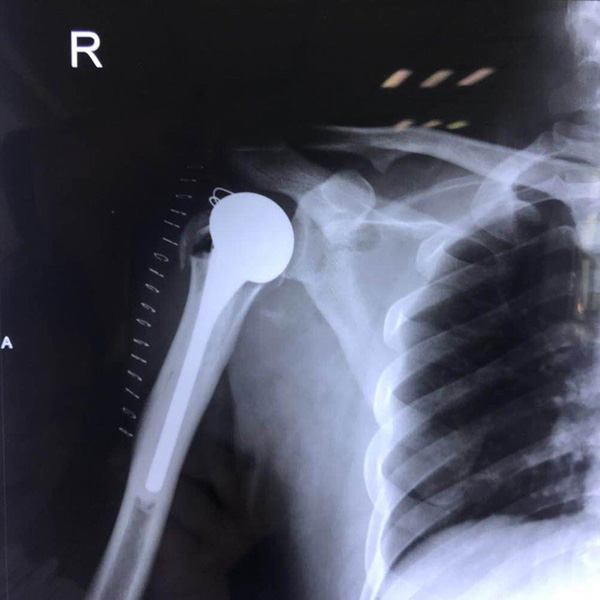

右側(cè)肱骨頭置換

患者郭某,男,40歲,因嚴(yán)重車禍導(dǎo)致“右肱骨頭粉碎性骨折”,一般的手術(shù)很難將粉碎的骨折塊拼接起來,即便大致的拼接起來,因?yàn)楣敲娴牟黄?.....